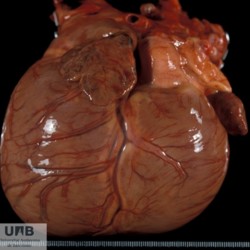

Etiquetes: N-519/97 1 total Canine Specie: Canine Organ: Heart Lesion: Cardiomyopathy Lesion modifier: Cardiomyopathy - Dilated Disease: - Files/Expedient: N-519/97 Not viewed Títol Select...Avian (Exotic) (110)Avian (Poultry) (76)Bovine (317)Canine (935)Caprine (47)Equine (257)Feline (326)Ferret (19)General (127)Marine mammal (22)Non-human primate (20)Ovine (328)Porcine (379)Rabbit (61)Reptile (38)Rodent (28)Wildlife (91) Format Select...- (60)Abomasum (37)Adrenal gland (10)Blood (7)Blood vessel (50)Body as a whole (19)Bone (57)Bone marrow (21)Brain (93)Cloaca (1)Diaphragm (2)Ear (5)Esophagus (39)Eye (16)Fetus (12)Gallbladder (23)Gizzard (2)Heart (265)Intestine (356)Joint (32)Kidney (443)Larynx (5)Liver (326)Lung (264)Lymph node (91)Mammary gland (10)Mediastinum (1)Muscle (22)Nasal cavity (22)Nerve (7)Omasum (5)Oral cavity (63)Ovary (14)Oviduct (8)Pancreas (7)Parathyroid (5)Penis (10)Peritoneum (65)Pharynx (9)Pituitary gland (6)Placenta (7)Prostate (8)Proventriculus (3)Reticulum (1)Rumen (28)Sinus (7)Skin (181)Spinal cord (15)Spleen (105)Stomach (125)Teeth (1)Testicle (11)Thoracic cavity (31)Thymus (13)Thyroid gland (5)Tongue (32)Tonsils (11)Trachea (11)Urethra (5)Urinay bladder (61)Uterus (27)Vagina (1)Vulva (1)Yolk sac (1) Cobertura Select...- (152)Abomasitis (26)Abscess (27)Acidosis (1)Adenocarcinoma (20)Adenoma (9)Aerosacculitis (6)Agenesis (1)Agnathia (1)Alopecia (7)Amyloidosis (12)Aneurysm (6)Angiectasis (1)Anthracosis (1)Arteritis (11)Arthritis (15)Arthrogryposis (6)Artifact (4)Ascites (13)Atelectasis (8)Atherosclerosis (5)Atresia (1)Atrial septal defect (2)Atrophy (10)Autolysis (7)Bronchitis (6)Bronchopneumonia (26)Cachexia (2)Carcinoma (103)Cardiomyopathy (19)Cellulitis (2)Chemodectoma (4)Cholangiohepatitis (4)Cholangitis (19)Cholecystitis (4)Cholestasis (5)Chondrodysplasia (2)Chondrosarcoma (2)Chronic passive congestion (13)Chylothorax (2)Cirrhosis (6)Coelomitis (3)Coenurus cerebralis (4)Colitis (40)Congestion (17)Conjunctivitis (5)Coronitis (3)Cryptorchidism (3)Cyst (25)Cystitis (24)Dermatitis (69)Diaphragmatic hernia (4)Dilation (28)Discospondylitis (1)Disseminated intravascular coagulation (7)Dyschondroplasia (1)Dysplasia (29)Ectopia cordis (1)Ectopic ureter (1)Edema (55)Emphysema (5)Encephalitis (5)Endocardiosis (14)Endocarditis (26)Endometritis (5)Enteritis (118)Enterolith (6)Epulis (3)Esophagitis (14)Fasciitis (1)Fibrosis (7)Fibrous osteodystrophy (8)Fistula (1)Folliculitis (3)Fracture (2)Gastritis (34)Gingivitis (5)Glioma (8)Glomerulonephritis (21)Glossitis (25)Glycogenosis (1)Gout (8)Granuloma (2)Granulosa cell tumor (4)Hemangioma (9)Hemangiosarcoma (46)Hematoma (8)Hemoglobinuria (2)Hemopericardium (12)Hemoperitoneum (2)Hemorrhage (100)Hemosiderosis (7)Hemothorax (2)Hepatitis (78)Hernia (11)Histiocytosis (3)Hydatid cyst (11)Hydrocephalus (9)Hydrometra (1)Hydronephrosis (22)Hydropericardium (6)Hydrothorax (3)Hydroureter (5)Hyperkeratosis (8)Hyperostosis (4)Hyperplasia (37)Hypertrophy (9)Hypopigmentation (1)Hypoplasia (7)Hypopyon (1)Impaction (6)Infarction (63)Insulinoma (6)Intussusception (5)Jaundice (17)Laminitis (2)Laryngitis (2)Leiomyoma (5)Leukemia (13)Lipidosis (36)Lipoma (7)Lymphadenitis (45)Lymphadenopathy (7)Lymphangiectasia (6)Lymphangitis (5)Lymphoma (221)Malacia (11)Malignant melanoma (15)Mast cell tumor (11)Mastitis (8)Megaesophagus (2)Melanosis (3)Melena (4)Meningioma (6)Meningitis (6)Meningocele (2)Meningoencephalitis (5)Mesothelioma (5)Methemoglobinemia (2)Mineralization (10)Mucocele (5)Mucometra (1)Multilobular bone tumor (1)Mummification (3)Myelofibrosis (1)Myocarditis (4)Myositis (5)Necrosis (81)Nephritis (113)Nephroblastoma (6)Nephrosclerosis (1)Nephrosis (14)Neuritis (1)Obstruction (13)Omasitis (4)Omphalitis (1)Omphalophlebitis (7)Orchitis (4)Osteoarthrosis (5)Osteomyelitis (9)Otitis (2)Palatoschisis (3)Pancreatitis (3)Panniculitis (3)Papilloma (7)Parakeratosis (14)Patent ductus arteriosus (6)Peliosis hepatis (1)Perforation (17)Pericarditis (35)Peritonitis (39)Persistent right aortic arch (1)Pharyngitis (2)Pheochromocytoma (2)Phlebitis (2)Placentitis (6)Pleuritis (21)Pleuropneumonia (24)Pneumonia (109)Pneumothorax (3)Polycystosis (14)Polyp (5)Polyserositis (6)Posthitis (1)Proctitis (4)Prolapse (3)Prostatitis (3)Proventriculitis (1)Pyelonephritis (24)Pyometra (6)Pyothorax (4)Rhinitis (11)Rumenitis (6)Rupture (24)Salpingitis (3)Sarcoma (57)Sclerosis (1)Scoliosis (2)Seminoma (2)Sequestrum (2)Serous atrophy (14)Sinusitis (7)Splenitis (14)Splenomegaly (9)Spondylitis (6)Spondylosis (1)Stenosis (9)Stomatitis (32)Tenosynovitis (2)Teratoma (3)Thricobezoar (2)Thrombosis (16)Tonsilitis (4)Torsion (13)Tracheitis (4)Tympany (7)Typhlitis (8)Typhlocolitis (4)Ulcer (43)Urethritis (1)Urolithiasis (36)Uroperitoneum (1)Uveitis (1)Vasculitis (15)Ventricular septal defect (3)Volvulus (11) Matèria Select... - (14)- (1653)- (152)Abomasitis - Catarrhal (2)Abomasitis - Catarrhal-hemorrhagic (1)Abomasitis - Chronic (1)Abomasitis - Fibrinous-necrotizing (2)Abomasitis - Hyperplasic (5)Abomasitis - Hyperplasic - Chronic (1)Abomasitis - Necrotic (1)Abomasitis - Necrotizing (2)Abomasitis - Ulcerative (5)Adenocarcinoma (9)Aerosacculitis - Granulomatous (1)Amyloidosis - Chronic (1)Arteritis - Necrotic (2)Arteritis - Necrotizing (1)Arthritis - Chronic (4)Arthritis - Fibrinous-purulent (3)Arthritis - Serous (4)Arthritis - Subacute (1)Ascites - Serous (1)Atrophy - Serous (1)Bronchitis - Catarrhal (3)Bronchitis - Suppurative (1)Bronchopneumonia - Catarrhal-purulent (17)Bronchopneumonia - Fibrinous (1)Bronchopneumonia - Granulomatous (1)Bronchopneumonia - Purulent (1)Bronchopneumonia - Suppurative (5)Carcinoma - Adenocarcinoma (33)Carcinoma - Adenocarcinoma - Hepatocellular (2)Carcinoma - Adenocarcinoma - Mucinous (1)Carcinoma - Basosquamous (1)Carcinoma - Cholangiocellular (3)Carcinoma - Hepatocellular (4)Carcinoma - Metastatic (3)Carcinoma - Squamous cell carcinoma (13)Carcinoma - Transitional cell (2)Cardiomyopathy - Dilated (13)Cardiomyopathy - Hypertrophic (6)Cellulitis - Necrotizing (1)Cholangitis - Chronic (8)Cholangitis - Hyperplasic (3)Cholecystitis - Fibrinous-necrotizing (1)Coelomitis - Fibrinous (1)Coelomitis - Granulomatous (1)Colitis - Catarrhal (3)Colitis - Catarrhal-hemorrhagic (1)Colitis - Fibrinous (1)Colitis - Fibrinous-necrotizing (1)Colitis - Fibrinous-necrotizing (Diphtheritic) (6)Colitis - Granulomatous (2)Colitis - Hemorrhagic (4)Colitis - Hemorrhagic-necrotizing (3)Colitis - Necrotizing (2)Colitis - Ulcerative (6)Congestion - Chronic (2)Conjunctivitis - Hyperplasic (1)Conjunctivitis - Purulent (3)Coronitis - Ulcerative (1)Cystitis - Chronic (3)Cystitis - Fibrinous (1)Cystitis - Fibrinous-necrotizing (1)Cystitis - Follicular (1)Cystitis - Hemorrhagic (6)Cystitis - Hemorrhagic-ulcerative (1)Cystitis - Necrotizing (9)Cystitis - Perforated (1)Dermatitis - Granulomatous (14)Dermatitis - Hyperkeratotic (10)Dermatitis - Hyperplasic (proliferative) (1)Dermatitis - Hyperplastic (10)Dermatitis - Necrotizing (4)Dermatitis - Pustular (4)Dermatitis - Ulcerative (2)Dilation - Chronic (1)Discospondylitis - Necrotizing (1)Dysplasia - Follicular (5)Edema - Interstitial (6)Emphysema - Interstitial (1)Encephalitis - Granulomatous (1)Encephalitis - Nonsuppurative (1)Endocardiosis - Mitral (7)Endocardiosis - Mitral - Chronic (5)Endocarditis - Valvular (6)Endocarditis - Valvular - Mitral (7)Endocarditis - Valvular - Pulmonic (1)Endocarditis - Valvular - Subacute (1)Endocarditis - Valvular - Subaortic (5)Endocarditis - Valvular - Tricuspid (4)Endometritis - Purulent (3)Endometritis - Purulent-hemorrhagic (2)Enteritis - Catarrhal (23)Enteritis - Catarrhal - Acute (1)Enteritis - Catarrhal-hemorrhagic (5)Enteritis - Catarrhal-hemorrhagic - Acute (2)Enteritis - Fibrinous (16)Enteritis - Fibrinous - Acute (3)Enteritis - Fibrinous-necrotizing (7)Enteritis - Granulomatous (14)Enteritis - Granulomatous - Chronic (1)Enteritis - Granulomatous - Multifocal (1)Enteritis - Hemorrhagic (17)Enteritis - Hemorrhagic - Acute (1)Enteritis - Hemorrhagic-necrotizing (1)Enteritis - Hyperplasic (proliferative) (4)Enteritis - Necrotizing (4)Enteritis - Necrotizing - Acute (1)Enteritis - Necrotizing - Hemorrhagic (1)Enteritis - Necrotizing-ulcerative (2)Enteritis - Ulcerative (1)Enteritis - Ulcerative-hemorrhagic (1)Esophagitis - Erosive-ulcerative (6)Esophagitis - Necrotizing (4)Esophagitis - Ulcerative (1)Esophagitis - Ulcerative-necrotizing (1)Fasciitis - Fibrinous-purulent (1)Folliculitis - Purulent (2)Gastritis - Catarrhal (2)Gastritis - Chronic (1)Gastritis - Follicular (1)Gastritis - Hemorrhagic (2)Gastritis - Hemorrhagic-necrotizing (1)Gastritis - Hypertrophic (2)Gastritis - Inclusion bodies (1)Gastritis - Mineralization (1)Gastritis - Mycotic (1)Gastritis - Necrotizing (2)Gastritis - Ulcerative (6)Gastritis - Uremic (3)Gingivitis - Erosive (2)Gingivitis - Hyperplasic (proliferative) (1)Gingivitis - Necrotizing (1)Glomerulonephritis - Chronic (7)Glomerulonephritis - Membranoproliferative (3)Glomerulonephritis - Membranoproliferative - Chronic (1)Glomerulonephritis - Membranous (3)Glomerulonephritis - Membranous - Chronic (1)Glomerulonephritis - Proliferative (2)Glomerulonephritis - Subacute (1)Glossitis - Erosive (2)Glossitis - Granulomatous (6)Glossitis - Hyperplasic (1)Glossitis - Hyperplasic (proliferative) (2)Glossitis - Hyperplastic (1)Glossitis - Necrotizing (2)Glossitis - Necrotizing - Focal (1)Glossitis - Ulcerative (6)Glossitis - Ulcerative - Multifocal (1)Glossitis - Ulcerative - Subacute (1)Glycogenosis (1)Granuloma - Eosinophilic (1)Hemangiosarcoma - Metastatic (2)Hemorrhage - Acute (1)Hemorrhage - Subcapsular (3)Hepatitis - Abscess (9)Hepatitis - Acute (3)Hepatitis - Chronic (4)Hepatitis - Chronic interstitial (6)Hepatitis - Granulomatous (7)Hepatitis - Interstitial - Multifocal (1)Hepatitis - Interstitial - Subacute (1)Hepatitis - Necrotizing (17)Hepatitis - Necrotizing - Acute (2)Hepatitis - Necrotizing - Hemorrhagic (1)Hepatitis - Necrotizing - Subacute (1)Hepatitis - Pyogranulomatous (7)Hepatitis - Subacute (4)Hydronephrosis - Chronic (1)Hydropericardium - Chronic (1)Hyperplasia - Erythroid (1)Hyperplasia - Lymphoid (3)Hyperplasia - Myeloid (1)Hyperplasia - Nodular (8)Hypertrophy - Concentric (2)Hypertrophy - Eccentric (3)Infarction - Acute (17)Infarction - Acute - Multifocal (2)Infarction - Chronic (5)Infarction - Chronic - Multifocal (1)Infarction - Subacute (18)Infarction - Subacute - Focal (2)Laminitis - Chronic (2)Laryngitis - Necrotic (1)Laryngitis - Necrotizing (1)Leukemia - Lymphoid leukemia (2)Leukemia - Non-lymphoid leukemia (6)Lipidosis - Multifocal (1)Lipidosis - Panlobular (1)Lipidosis - Panlobular - Generalized (2)Lymphadenitis - Granulomatous (24)Lymphadenitis - Granulomatous - Chronic (3)Lymphadenitis - Hemorrhagic (1)Lymphadenitis - Necrotizing (5)Lymphadenitis - Necrotizing (caseous) (11)Lymphangitis - Granulomatous (1)Lymphangitis - Purulent (1)Lymphangitis - Ulcerative (1)Lymphoma - Alimentary lymphoma (7)Lymphoma - Cutaneous lymphoma (6)Lymphoma - Lymphosarcoma (2)Lymphoma - Mediastinal lymphoma (1)Lymphoma - Multicentric lymphoma (29)Malignant melanoma - Malignant (1)Malignant melanoma - Metastatic (1)Mast cell tumor - Metastatic (1)Mastitis - Fibrinous-purulent (2)Mastitis - Necrotic (1)Mastitis - Purulent (3)Mastitis - Suppurative (1)Meningitis - Fibrinous-purulent (2)Meningitis - Purulent (4)Meningoencephalitis - Necrotizing (3)Meningoencephalitis - Nonsuppurative (2)Mineralization - Metastatic (4)Myocarditis - Fibrous - Chronic (1)Myocarditis - Granulomatous (1)Myositis - Purulent (2)Necrosis - Acute (1)Necrosis - Cortical (5)Necrosis - Follicular (1)Necrosis - Papillary (8)Necrosis - Papillary - Acute (3)Necrosis - Subacute (3)Necrosis - Tubular (6)Nephritis - Embolic (2)Nephritis - Embolic suppurative (7)Nephritis - Granulomatous (27)Nephritis - Granulomatous - Chronic (1)Nephritis - Granulomatous - Multifocal (1)Nephritis - Interstitial (6)Nephritis - Interstitial - Acute (4)Nephritis - Interstitial - Chronic (41)Nephritis - Interstitial - Subacute (12)Nephritis - Purulent (7)Nephritis - Purulent - Acute (2)Nephritis - Purulent - Multifocal (3)Nephrosis - Cholemic (3)Nephrosis - Hemoglobinuric (10)Omasitis - Fibrinous-necrotizing (1)Omasitis - Hyperkeratotic (1)Omasitis - Necrotizing (2)Omphalophlebitis - Fibrinous-purulent (2)Omphalophlebitis - Purulent (3)Orchitis - Necrotizing (1)Osteomyelitis - Necrotizing (7)Osteomyelitis - Purulent (2)Otitis - Necrotizing (1)Otitis - Proliferative (1)Pancreatitis - Acute (1)Pancreatitis - Chronic (1)Pancreatitis - Granulomatous (1)Panniculitis - Fibrinous-purulent (1)Panniculitis - Necrotic (1)Panniculitis - Parasitic (1)Perforation - Acute (2)Pericarditis - Fibrinous (19)Pericarditis - Fibrinous - Subacute (1)Pericarditis - Fibrinous-necrotizing (1)Pericarditis - Fibrinous-purulent (3)Pericarditis - Fibrous (1)Pericarditis - Fibrous - Chronic (1)Pericarditis - Gangrenous (6)Pericarditis - Granulomatous (1)Pericarditis - Granulomatous - Chronic (2)Peritonitis - Acute (1)Peritonitis - Fibrinous (11)Peritonitis - Fibrinous - Subacute (1)Peritonitis - Fibrinous-purulent (5)Peritonitis - Fibrous (3)Peritonitis - Granulomatous (6)Peritonitis - Purulent (1)Peritonitis - Purulent-hemorrhagic (1)Peritonitis - Pyogranulomatous (3)Pharyngitis - Fibrinous-necrotizing (1)Pharyngitis - Ulcerative (1)Pheochromocytoma - Metastatic (1)Phlebitis - Purulent (1)Placentitis - Fibrinous-necrotizing (1)Placentitis - Necrotic (1)Placentitis - Necrotizing (1)Pleuritis - Chronic (1)Pleuritis - Fibrinous (3)Pleuritis - Fibrinous-purulent (2)Pleuritis - Fibrous (2)Pleuritis - Granulomatous (3)Pleuritis - Hyperplastic (2)Pleuritis - Purulent (2)Pleuritis - Pyogranulomatous (1)Pleuropneumonia - Fibrinous (13)Pleuropneumonia - Fibrinous-necrotizing (5)Pleuropneumonia - Granulomatous (2)Pleuropneumonia - Hemorrhagic-necrotizing (4)Pneumonia - Aspiration (11)Pneumonia - Bronchointerstitial (4)Pneumonia - Bronchointerstitial - Subacute (1)Pneumonia - Embolic (5)Pneumonia - Granulomatous (37)Pneumonia - Granulomatous - Multifocal (4)Pneumonia - Hemorrhagic-necrotizing (2)Pneumonia - Interstitial (7)Pneumonia - Interstitial - Acute (8)Pneumonia - Interstitial - Chronic (6)Pneumonia - Interstitial - Subacute (15)Pneumonia - Necrotizing (2)Pneumonia - Pyogranulomatous (2)Pneumonia - Verminous (5)Polyserositis - Fibrinous (6)Polyserositis - Fibrous (1)Proctitis - Fibrinous-necrotizing (1)Proctitis - Parasitic (2)Prostatitis - Purulent (1)Pyelonephritis - Acute (2)Pyelonephritis - Chronic (3)Rhinitis - Catarrhal (2)Rhinitis - Fibrinous (1)Rhinitis - Granulomatous (4)Rhinitis - Purulent (3)Rumenitis - Acute (1)Rumenitis - Erosive (1)Rumenitis - Necrotizing (1)Rupture - Acute (3)Sarcoma - Fibrosarcoma (12)Sarcoma - Hemangiosarcoma (11)Sarcoma - Histiocytic (7)Sarcoma - Metastatic (1)Sarcoma - Multilobular tumor of bone (1)Sequestrum - Chronic (2)Sinusitis - Suppurative (1)Splenitis - Granulomatous (8)Splenitis - Granulomatous - Chronic (1)Splenitis - Necrotizing (3)Splenitis - Necrotizing (caseous) (2)Spondylitis - Necrotizing (2)Stenosis - Intestinal (1)Stenosis - Valvular - Subaortic (4)Stomatitis - Erosive (12)Stomatitis - Erosive-ulcerative (3)Stomatitis - Fibrinous-necrotizing (1)Stomatitis - Fibrinous-necrotizing (Diphtheritic) (1)Stomatitis - Granulomatous (1)Stomatitis - Hyperplasic (1)Stomatitis - Hyperplasic (proliferative) (1)Stomatitis - Necrotizing (2)Stomatitis - Ulcerative (5)Stomatitis - Ulcerative - Multifocal (1)Stomatitis - Ulcerative-necrotizing (1)Tonsilitis - Necrotizing (4)Torsion - Acute passive hyperemia (5)Tracheitis - Catarrhal (3)Tracheitis - Fibrinous (1)Tracheitis - Granulomatous (1)Typhlitis - Catarrhal (1)Typhlitis - Fibrinous-necrotizing (2)Typhlitis - Hemorrhagic (2)Typhlitis - Ulcerative-hemorrhagic (1)Typhlocolitis - Fibrinous-necrotizing (2)Typhlocolitis - Proliferative (1)Ulcer - Chronic (6)Ulcer - Multifocal (2)Ulcer - Mycotic (1)Ulcer - Perforated (6)Urethritis - Hemorrhagic (1)Urolithiasis - Chronic (2)Uveitis - Granulomatous (1)Vasculitis - Granulomatous (1)Vasculitis - Necrotizing (1) Editor Select...- (1970)Acidosis (2)Actinobacillosis (Pleuropneumonia) (11)Aelurostrongylosis (2)African horse sickness (13)African swine fever (14)Alopecia X (1)Anaplasmosis (4)Anthrax (2)Aortic thromboembolism (feline) (7)Ascariasis (15)Aspergillosis (18)Atopic dermatitis (1)Atrophic rhinitis (3)Babesiosis (6)Blackhead (1)Bluetongue (11)Border disease (2)Bovine viral diarrhea (21)Brucellosis (2)Candidiasis (5)Canine distemper (14)Caprine arthritis-encephalitis (2)Capture myopathy (1)Cardiac insufficiency (17)Caseous lymphadenitis (7)Chlamydiosis (2)Classical swine fever (19)Clostridiosis (19)Coccidiosis (9)Coenurosis (4)Colibacillosis (21)Contagious ecthyma (7)Copper toxicosis (11)Cowdriosis (Heartwater) (3)Cryptococcosis (3)Cryptosporidiosis (2)Cysticercosis (23)Demodicosis (1)Diabetes (1)Dicrocoeliosis (5)Dictyocaulosis (4)Dirofilariasis (7)Discoid lupus erythematosus (3)Echinococcosis (17)Edema disease (7)Egg drop syndrome (1)Encephalitozoonosis (5)Enterotoxemia (1)Enzootic bovine leukosis (46)Epitheliogenesis imperfecta (3)Equine rhinopneumonitis (2)Equine verminous arteritis (strongylosis) (7)Erysipelas (5)Exudative epidermitis (7)Fasciolasis (11)Feline eosinophilic dermatoses (1)Feline hepatic lipidosis (8)Feline histiocytosis (4)Feline infectious peritonitis (38)Feline leukemia (4)Feline lower urinary tract disease (3)Feline panleukopenia (16)Feline viral rhinotracheitis (1)Flea allergy dermatitis (1)Foot and mouth disease (2)Gasterophilosis (4)Glasser's disease (15)Gousiekte (4)Gout (6)Haemonchosis (9)Hemolytic anemia (4)Hemorrhagic diathesis (1)Hepatic insufficiency (11)Hepatosis dietetica (7)Herpesvirosis (6)Hyperadrenocorticism (7)Hyperparathyroidism (10)Hypertrophic osteopathy (6)Hypervitaminosis D (1)Hypodermosis (1)Inclusion body hepatitis (4)Infectious bovine rhinotracheitis (5)Infectious bronchitis (5)Infectious canine hepatitis (13)Influenza (4)Juvenile nephropathy (8)Lamb dysentery (4)Leishmaniasis (28)Leptospirosis (1)Leukosis (5)Listeriosis (4)Lumpy skin disease (3)Maedi-visna (4)Malignant catarrhal fever (12)Mange (6)Mannheimiosis (5)Marek's disease (7)Metabolic bone disease (2)Mucoid enteropathy (5)Mulberry heart disease (5)Myasis (1)Mycobacteriosis (22)Mycosis fungoides (6)Myxomatosis (3)Necrobacillosis (5)Neonatal isoerythrolysis (6)Nocardiosis (4)Oestrosis (2)Onchocerciasis (1)Osteochondrosis (1)Ostertagiosis (6)Ovine pulmonary adenocarcinoma (5)Oxyuriasis (1)Pacheco's disease (4)Papillomatosis (6)Paratuberculosis (18)Parvovirosis (17)Pasteurellosis (11)Pemphigus foliaceus (1)Periodontal disease (1)Polioencephalomalacia of ruminants (4)Polyarteritis nodosa (3)Polycystic kidney disease (13)Porcine circovirosis (11)Porcine dermatitis and nephropathy syndrome (9)Porcine proliferative enteropathy (4)Porcine reproductive and respiratory syndrome (6)Porcine stress syndrome (1)Pox (13)Pregnancy toxemia (3)Proventricular dilatation disease (2)Pseudotuberculosis (yersiniosis) (2)Psittacine beak and feather disease (PBFD) (5)Pyoderma (4)Q fever (4)Rabbit hemorrhagic disease (2)Renal insufficiency (12)Reticuloendotheliosis (2)Rhodococcosis (1)Rickets (1)Rinderpest (2)Salmonellosis (34)Sarcosporidiosis (2)Schmallenberg (7)Septicemia (23)Spirocercosis (11)Streptococcosis (5)Strongylosis (1)Swine dysentery (5)Systemic coronavirosis (5)Tetralogy of Fallot (5)Theileriosis (13)Thromboembolism (5)Toxoplasmosis (11)Transmissible viral proventriculitis (1)Traumatic reticuloperitonitis (3)Traumatism (16)Tuberculosis (58)Ulcerative lymphangitis (1)Uremic syndrome (20)Viral arthritis (6)White muscle disease (9)Wobbler syndrome (2)Xanthomatosis (1)Zygomycosis (4) Idioma Select...- (1180)Bacterial (501)Degeneration (106)Fungal (46)Hemodynamic (112)Idiopathic (22)Inflammation (58)Malformation (88)Neoplasia (343)Nutritional (41)Parasitic (243)Physical/Chemical (93)Toxic (44)Viral (304) Ítem destacat Porcine Sow. Porcine Ulcerative Dermatitis Syndrome (PUDS). Interface dermatitis. Lesions were neither painful nor pruritic. University of Pretoria, South…